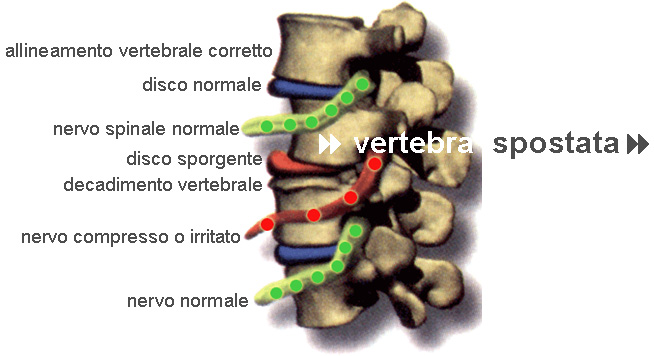

La Sublussazione Vertebrale

Oggetto principale dell’attività chiropratica è la sublussazione vertebrale. Esiste la sublussazione quando una vertebra perde il normale allineamento superiore ed inferiore, oppure quando una vertebra perde il suo movimento normale. Queste posizioni o movimenti impropri delle vertebre possono irritare, torcere, stirare o comprimere questi nervi delicati, impedendo all’energia vitale di scorrere correttamente attraverso il nostro corpo. Come conseguenza della comunicazione essenziale ostacolata, l’appropriato funzionamento dei tessuti, organi e sistemi forniti da questi nervi può risultare compromesso.

I CINQUE COMPONENTI DELLA SUBLUSSAZIONE

1. CHINESIOPATOLOGIA SPINALE: (Disallineamenti vertebrali ed alterazioni della mobilità spinale). Traumi fisici, chimici e mentali/emotivi possono causare gli squilibri vertebrali e provocare gli altri quattro componenti.

2. NEUROPATOLOGIA: (Danno e disfunzioni del sistema nervoso). Una scorretta mobilità o malposizione della ossa vertebrali, può irritare, torcere, stirare e comprimere nervi e tessuti neurologici delicati. Questo può danneggiare la funzionalità dei tessuti, degli organi e dei sistemi controllati da questi nervi.

4. ISTOPATOLOGIA: (Alterata funzionalità dei tessuti molli – dischi, legamenti, tendini). Anche i dischi intervertebrali, i legamenti ed altri tessuti molli possono essere oggetto di disfunzioni. Questi importanti tessuti hanno una scarsa irrorazione sanguigna; pertanto, il più delle volte, richiedono cure costanti anche dopo l’alleviarsi dei sintomi.

5. PATOFISIOLOGIA SPINALE: (Decadimento della colonna e disfunzionamento dell corpo). Con il tempo, la salute della colonna vertebrale degenera ed il corpo risponde con l’insorgenza di becchi osteofitici (sporgenze dell’osso), i quali si fondono tra loro, creando blocchi vertebrali. Anche altri organi e tessuti possono degenerare, se i nervi a loro afferenti sono stati danneggiati.